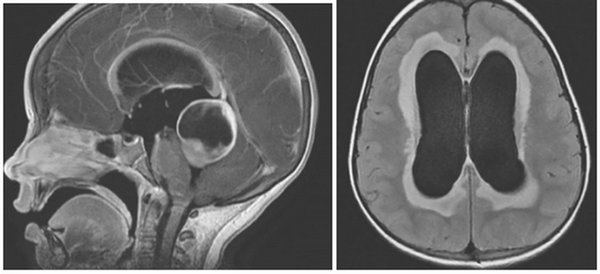

Внутренняя тривентрикулярная окклюзионная гидроцефалия на МРТ во фронтальной и сагиттальной плоскостях: на левом снимке видно гигантское кистозно-солидное образование, явившееся причиной обструкции ликворопроводящих путей на уровне Сильвиева водопровода